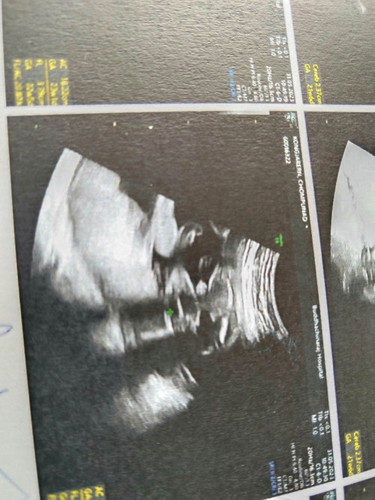

คุณหมอบอกว่า ได้ผู้ชายย♥️😅